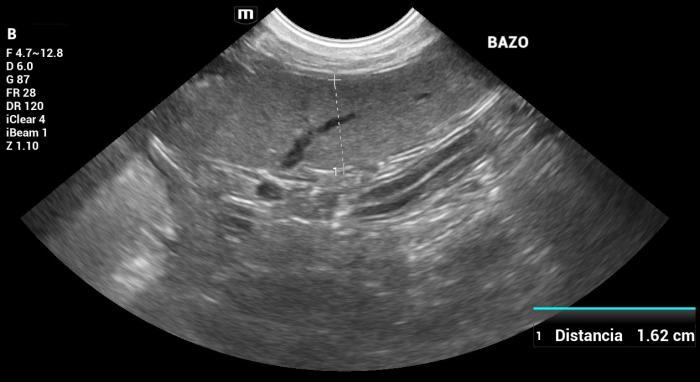

Además, se encontraron imágenes compatibles con mielolipomas. No se observaron otras lesiones esplénicas ni alteraciones relevantes en órganos abdominales evaluados (Figura 8).

Hallazgos ultrasonográficos (modo B y doppler color): El bazo se encontraba marcadamente agrandado en todos sus ejes, alcanzando la región mesogástrica derecha, con un espesor a nivel del cuerpo de 3.13 cm. Su conformación mostraba plegamiento parcial, compatible con cambios por desplazamiento, aumento de volumen o pérdida de soporte abdominal.

Además, se observaron indicios ecográficos de nefropatía crónica y de hígado graso.